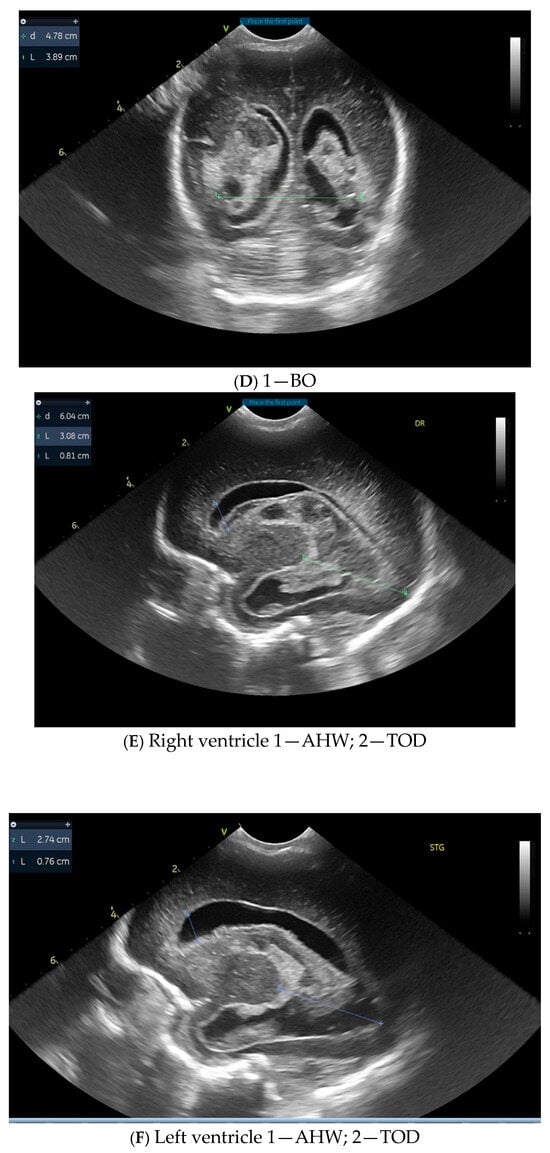

3. Results